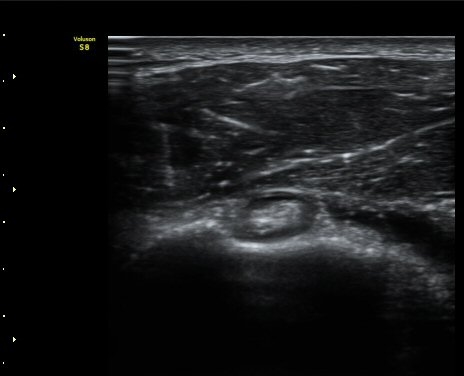

ŽÃËÀÚ¸¦ ¿À±¸µ¹±â ¾Æ·¡·Î ±æ°Ô ´ë°í °üÂûÇÏ´Ï ¿À±¸µ¹±â ¾Æ·¡, ¼ÒÈä±Ù ½ÉÃø¿¡ ¼ö¾×Àú·ù°¡

°üÂûµÇ¾î ¿À±¸µ¹±âÇÏÁ¡¾×³¶¿°À» ½Ã»çÇÑ´Ù(»çÁø 5).